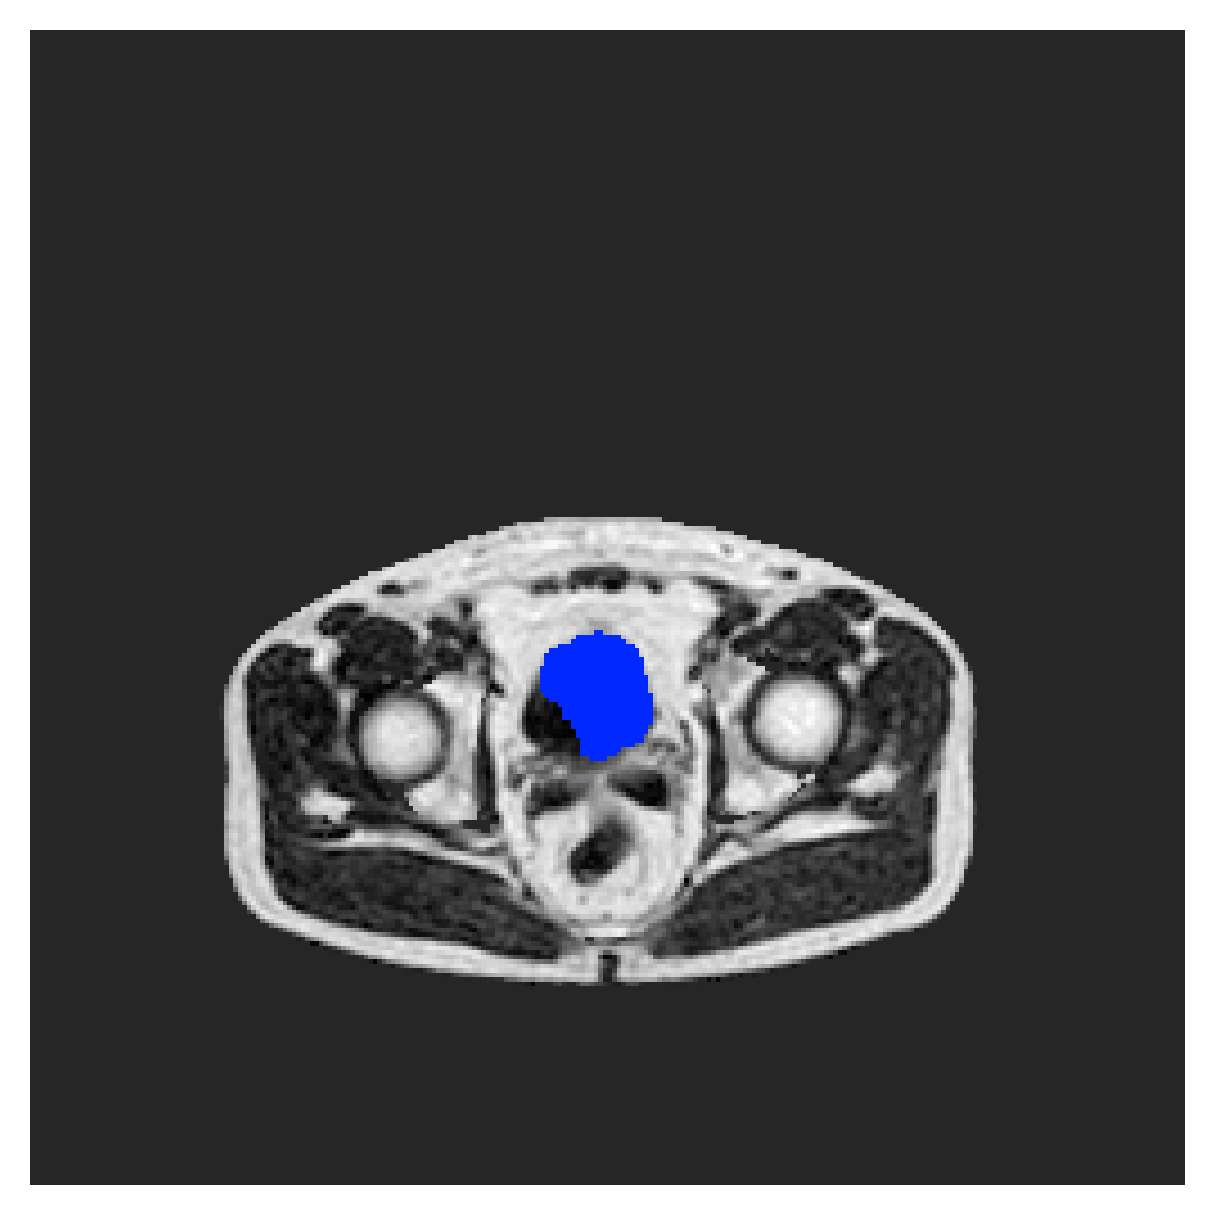

Qualitative comparison

|

In Figure 6 we provide qualitative results on a number of randomly chosen test set slices. Upon visual inspection, we can observe that training with the intensity-aware distances (particularly with and ) follows the image gradients better and is better at recovering the underlying shape than the Euclidean version. The CRF-loss seems to recover the shape of the myocardium and left ventricle to some extent, but fails entirely on the right ventricle.